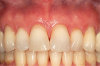

A female patient presented with composite restorations along the gingival margins that had been placed in an attempt to correct the appearance of gingival recession (Figure 13). The extent of the recession was visible in her smile, and the patient desired improved esthetics.

After 2 years, the FGM position was maintained in a coronal position relative to where it had been preoperatively (Figure 16). Stable root coverage was achieved, along with an esthetic enhancement to the patient's smile.

Fig 13. Preoperative retracted view showing extent of recession in a patient with composite restorations that had been placed to cover exposed roots and noncarious cervical lesions.

Fig 16. At 2 years postoperative, root coverage had been maintained and there was an overall enhanced and more natural appearance to the tissue.